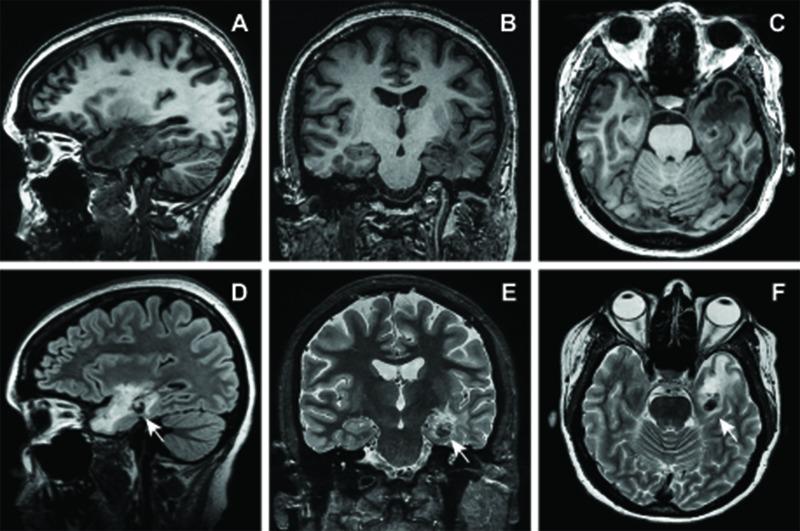

Stereotactic radiosurgery (SRS) is a promising treatment for medically intractable mesial temporal lobe epilepsy. SRS for epilepsy has had an acceptable safety profile with reports of radiation-induced vascular malformations confined to central nervous system pathologies with prominent angiogenesis - namely, primary brain tumors, metastases, and arteriovenous malformations. Theoretical risks for radiation-induced lesions following radiosurgery for epilepsy have yet to be established. Of 13 patients treated in a pilot trial for medial temporal lobe epilepsy, one developed multiple delayed radiation-induced cavernous malformations following radiosurgery. This patient received a prescription dose of 20 Gy delivered to the amygdala, anterior hippocampus, and parahippocampal gyrus. Eight years following treatment, computed tomography imaging demonstrated an evolving hyperdensity in the mesial temporal lobe. Magnetic resonance imaging confirmed multiple T2 hypointense lesions with a mixed-signal intensity core in the left parahippocampal gyrus and anterior temporal lobe. The patient was initially managed conservatively. However, recurrent hemorrhage ultimately caused an acute deterioration in mental status, aphasia, and hemiparesis, necessitating surgical resection. Pathology confirmed radiation-induced cavernous malformations. This represents the first case of a radiation-induced vascular lesion as a long-term sequela of radiosurgery for epilepsy and illustrates the potential for this complication even when low doses are used in patients without angiogenic lesions. Optimal timing and indications for surgical resection of radiation-induced cavernous malformations prior to the development of neurologic symptoms warrant further refinement. Long-term vigilance and clinical monitoring are required.

立体定向放射外科手术(SRS)是治疗药物难治性内侧颞叶癫痫的一种有前景的方法。用于癫痫的SRS具有可接受的安全性,有报告称辐射诱发的血管畸形局限于具有显著血管生成的中枢神经系统病变,即原发性脑肿瘤、转移瘤和动静脉畸形。癫痫放射外科手术后辐射诱发病变的理论风险尚未确定。在一项内侧颞叶癫痫的试点试验中治疗的13例患者中,有1例在放射外科手术后出现了多个延迟性辐射诱发的海绵状畸形。该患者接受了20 Gy的处方剂量,照射杏仁核、前海马体和海马旁回。治疗8年后,计算机断层扫描成像显示内侧颞叶出现逐渐发展的高密度影。磁共振成像证实左侧海马旁回和颞叶前部有多个T2低信号病变,核心为混合信号强度。患者最初采用保守治疗。然而,反复出血最终导致精神状态急性恶化、失语和偏瘫,需要进行手术切除。病理证实为辐射诱发的海绵状畸形。这是首例作为癫痫放射外科手术长期后遗症的辐射诱发血管病变,表明即使在没有血管生成病变的患者中使用低剂量时,这种并发症也有可能发生。在神经症状出现之前,手术切除辐射诱发的海绵状畸形的最佳时机和适应证有待进一步完善。需要长期的警惕和临床监测。